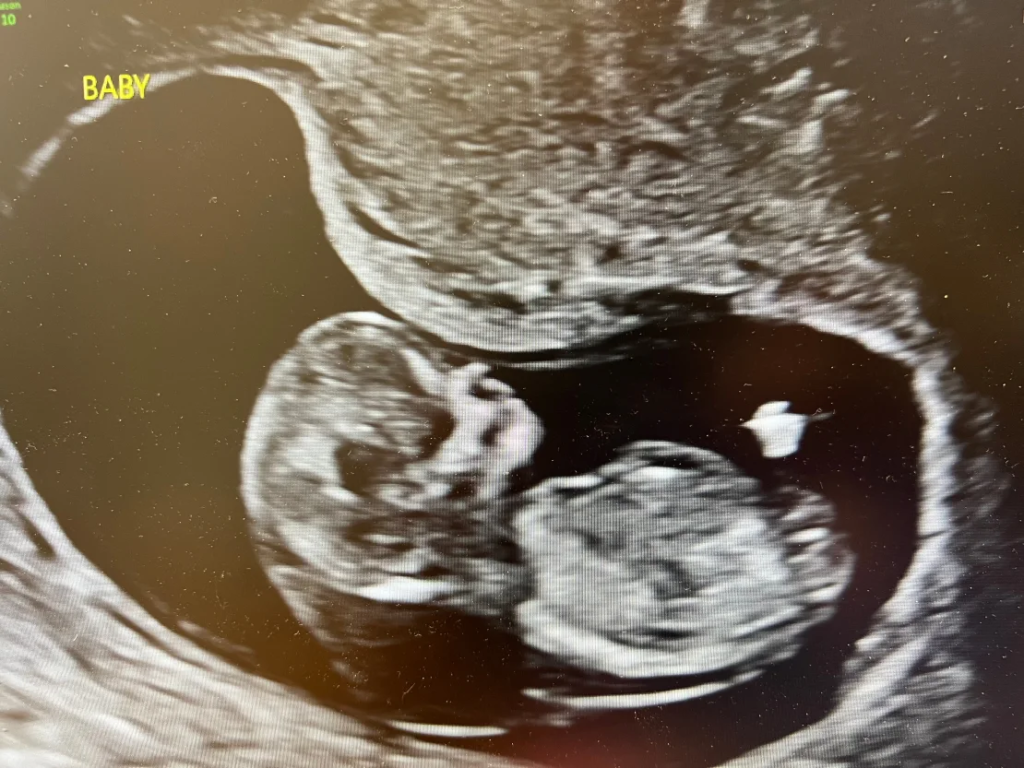

The Adkinses had hoped for better from the state they loved. John’s family goes back six generations in Idaho, and they’re raising their 2-year-old son here. Last year, they were overjoyed to learn that he was going to be a big brother; they’d always wanted a big family. But 12 weeks into the pregnancy, their plans were shattered during a routine ultrasound.

“As soon as that ultrasound technician put that wand on my stomach and I saw the baby on the screen, I knew something was wrong,” Jen told CNN. “I could just tell, ‘that’s a lot of fluid that’s not supposed to be there.’”

A genetic counselor and a maternal-fetal medicine specialist told Jen that it was very likely the fetus had Turner syndrome, a disorder in which a baby assigned female at birth is born with one missing or partial X chromosome.

Research shows that it results in miscarriage in more than 90% of cases and can cause abnormalities in the heart and kidneys, restricted growth and — most clear to Jen — excess fluid around the neck, called cystic hygroma, and severe swelling or edema, called hydrops.

“Essentially, they were surprised I was still pregnant, based on the severity of what they were seeing on the ultrasound,” Jen recalled.